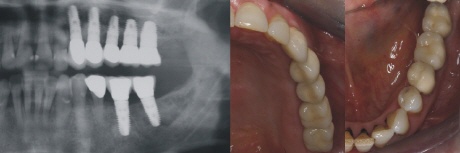

Versorgung

Jedes Implantat wird mit einer einzelnen Krone versorgt, da dadurch höchste Genauigkeit und beste Pflegemöglichkeit gewährleistet wird. Der Implantologe nennt diese Variante eine Versorgung mit Einzelzahnkronen oder auch eine „Zahn zu Zahn“ Versorgung im Gegensatz zu einer implantatgetragenen Brücke, die im Oberkiefer ebenfalls auf nur drei Implantaten theoretisch möglich wäre.